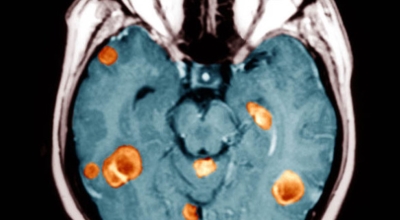

가장 흔한 뇌종양은 수막종이며 종양의 크기나 위치에 따라 수술이 필요하지 않을 수 있지만 청각 신경초종은 이명을 발생시킬 수 있다고 하며 심한 경우 안면 마비, 경련 및 통증을 발생시킬 수 있지만 뇌종양은 생존을 좌우하게되는 교모세포종 문제가 뒤늦게 생기는 것으로 주의가 필요한 이유이예요.

뇌종양이 악성인 경우, 빨리 자라는 특성이 있기 때문에 수술적으로 절제가 필요할 수 있습니다. 하지만 수술로 종양이 완벽하게 제거가 어려운 경우, 수술 후에 방사선 치료와 항암치료를 추가적으로 시행되어요. 요즘 들어서 뇌조직의 훼손을 최소화하고 수술 흉터가 거의 남지 않는 방법으로 하는 치료인 감마나이프 방사선 수술이 있답니다. 이 방사선 수술은 전신 마취와 피부 절개가 필요 없으며, 합병증이나 후유증이 적은 것으로 알려져 있답니다.

종양의 부위가 너무 커서 다른 방법을 활용하기 어렵거나 신경학적으로 생기는 증상이 너무 심하다고 판단이 될 경우에 활용할 수 있답니다. 하지만 다발성 병변으로 발생한 종양이거나 면역력이 많이 떨어져 있는 등 전신이 쇠약한 환자의 경우, 신중하게 생각해보아야 해요.